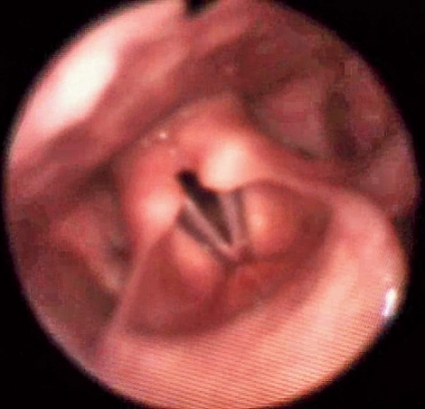

I vårt material hade många patienter supraglottisk obstruktion, och dessa kan i vissa fall opereras med framgång. Vårt material växer stadigt, och vi ser olika bilder av supraglottisk kollaps (Figur 1 och 2), ibland glottisk adduktion (Figur 3) eller en kombination av dessa (Tabell I). I de fall där man påvisar glottisk adduktion (EI-VCD) kan operation inte rekommenderas, och det är ovisst om vi i framtiden kan erbjuda dessa patienter någon hjälp. Andningsteknik i samråd med logoped och/eller sjukgymnast [11] är en möjlig väg att gå, men effekten är svår att utvärdera.